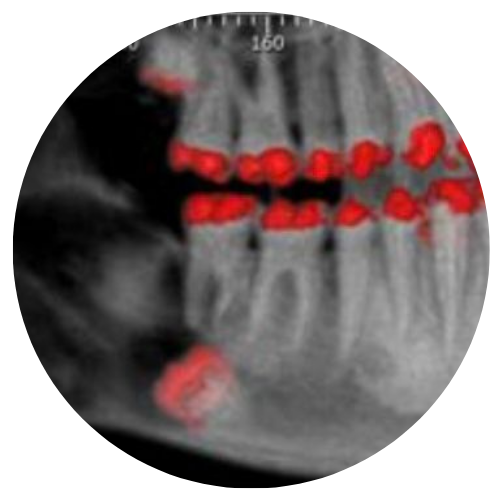

Os tumores benignos dos maxilares e/ou lesões de origem dentaria, são diagnosticados e tratados por nossa equipe; baseados em mais de duas décadas de experiência em cirurgia bucomaxilofacial.